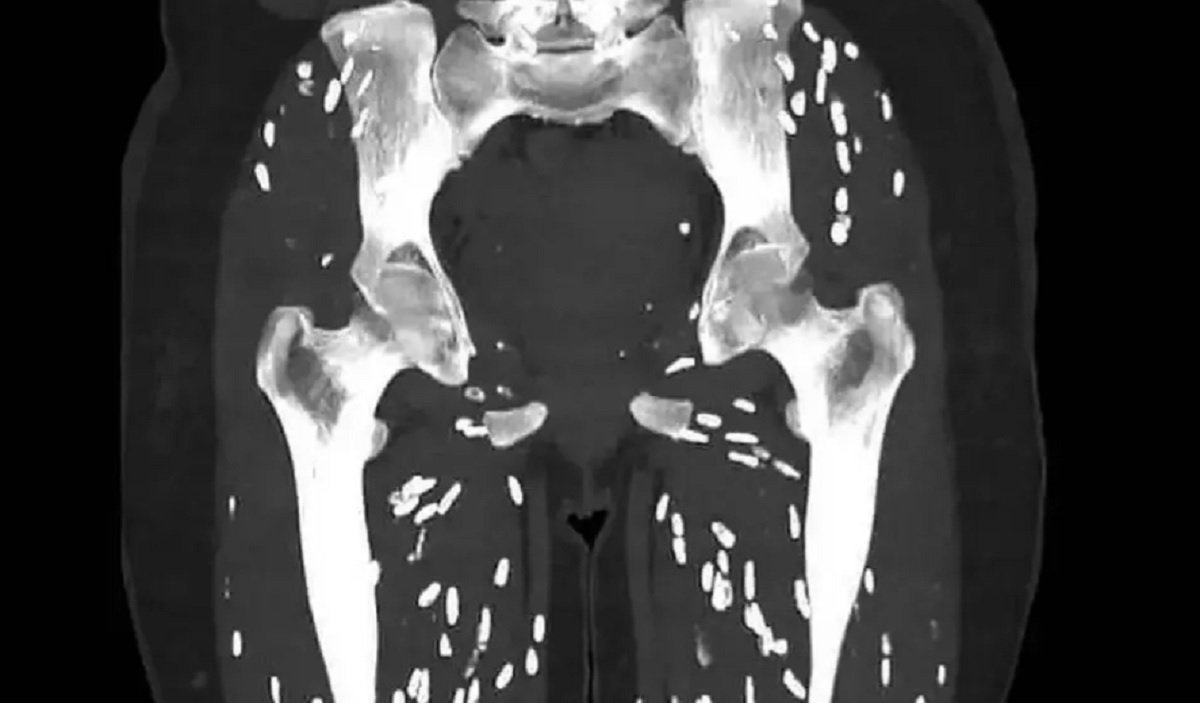

Dokter Sam Ghali, yang memiliki lebih dari 630 ribu pengikut di X, membagikan foto hasil CT scan tersebut dan meminta pengikutnya menebak diagnosisnya. Dia menggambarkan gambar itu sebagai salah satu CT scan paling gila yang pernah dia lihat.

CT scan yang dibagikan menunjukkan respons inflamasi tubuh terhadap sistiserkosis, yang membunuh larva dan menyebabkan kalsifikasi, dikenal sebagai kalsifikasi butiran beras karena penampilannya.